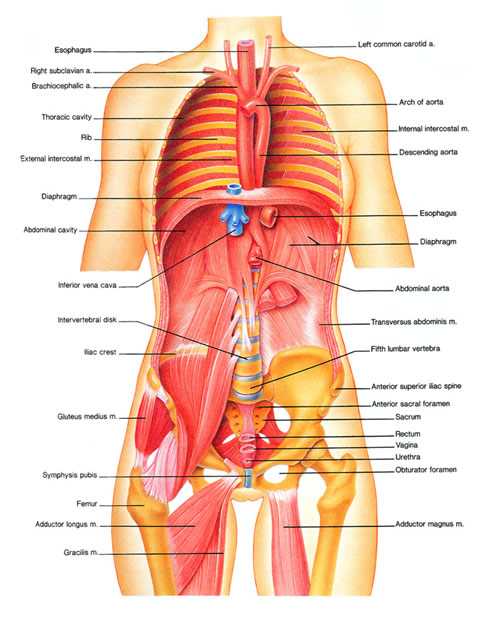

Intro to Anatomy 6: Tissues, Membranes, Organs – Freethought Forum

anatomy of torso organ

Abdominal and Pelvic Pain in the Nonpregnant Female | Tintinalli’s …

Anatomical Positions – SCIENTIST CINDY

Lower Back Muscle Anatomy and Low Back Pain

Anatomy Of Female Human Body From The Back – Male Muscle Model – As …